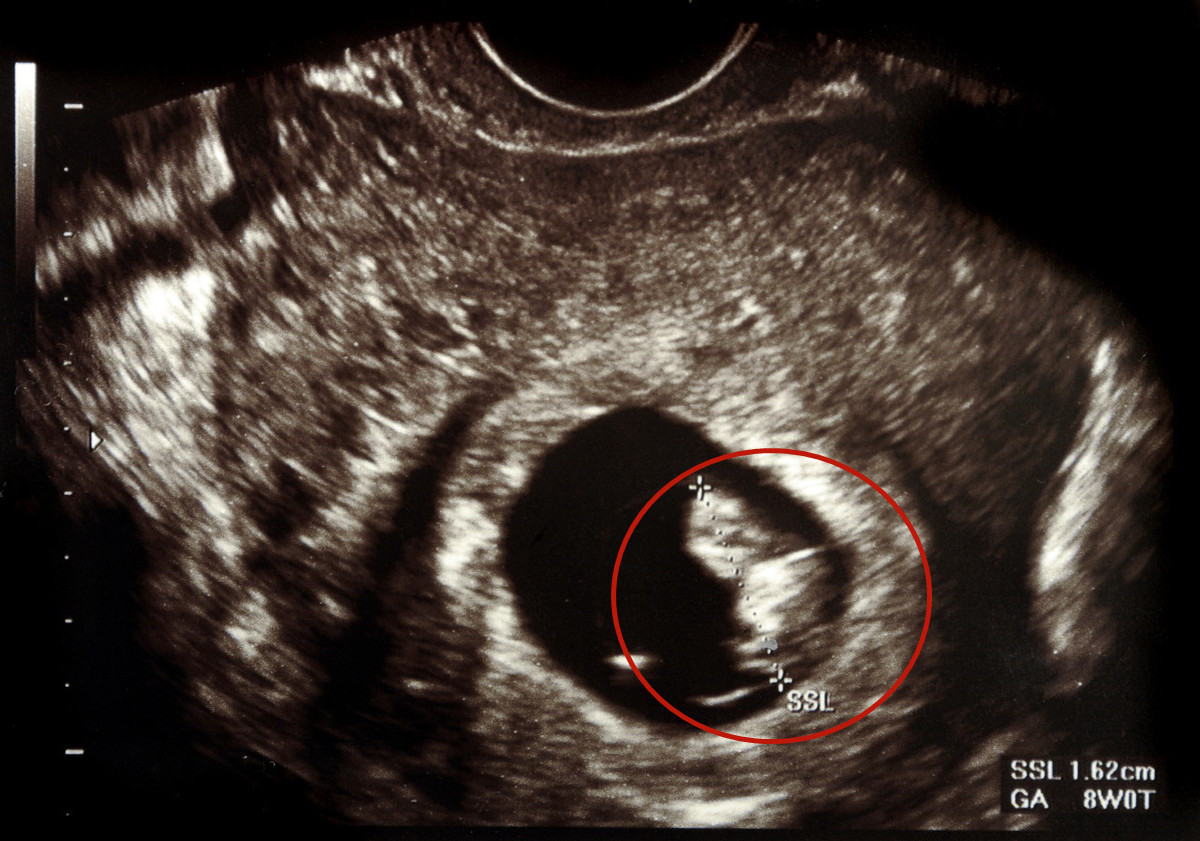

孕期的孕检有着严格的时间、项目规定,每位妈妈都不敢对此大意,生怕因为自己的疏忽影响了胎宝的健康,可又有多少孕妈能够真正读懂“孕检报告”呢?你知道所谓的“孕囊、胎心、胎芽”意味着什么吗?

“宫内早孕未见胎心”四个明晃晃的大字写在了B超单上,也正是因为这四个字,让莉莉认为是“胎儿不在了”,这才突然情绪崩溃放声大哭。

B超单怎么看孕囊、胎心、胎芽?能读懂的孕妈,秒知胎儿发育状况

1)孕囊的大小

在孕5周左右的时候,通过B超就可以清晰地看到孕囊,随着孕期的逐步增长,孕囊会慢慢演变为人的模样。那如何判断妊娠期胚胎是否正常,我们就需要通过孕囊的大小、位置还有形状来进行分析判断。

孕6周的时候,孕囊的大小直径约为2CM,其内可见卵黄囊以及胎心搏动;在孕10周时候,孕囊的大小直径约为5cm,其内可见月3.5cm的胎芽以及胎心搏动,如果在此期间孕囊的数据在这个范围内,则代表发育正常。

2)孕囊的形状

通过孕囊的尺寸我们可以看得出来,孕囊基本上为圆形或者椭圆形:

- 如果B超单上写着:外形清晰、轮廓完整视则表示发育正常;

- 如果在B超检测发现孕囊的形状不规则、或者模糊轮廓不清晰,位置在靠近子宫宫颈部位,而孕妇又伴有腹痛或者流血的现象,就说明有流产的先兆。